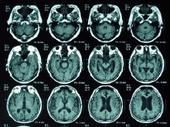

(3)CT掃描SNPH時顯示腦室擴大,其特點是側腦室額角呈圓球形,伴腦室周圍(特別是額角)低密度區,提示腦脊液經腦室壁的室管膜代償性吸收致腦室周圍水腫,而腦溝不受影響,此特點可與腦萎縮的改變相區別。

凡有上述情況,就要考慮到SNPH的可能性,並及時做顱腦CT或MRI掃描、核素腦池造影或碘水腦池CT掃描等檢查,可望獲得早期診斷。